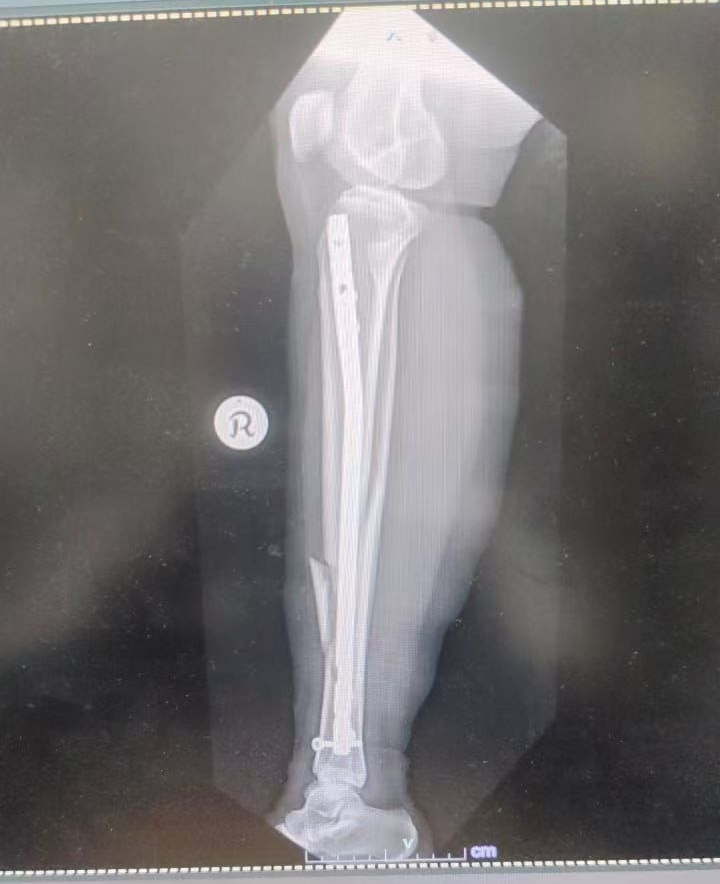

Figure 3: Final X-ray

Figure 4: Final X-ray